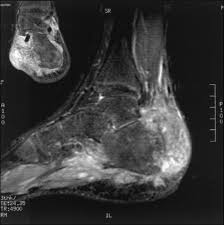

Foot melanoma refers to cancer of the cells in the top layer of the skin on the foot. What bone metastasis looks like. Local treatments focus on just the bone or bones where the cancer spread. There are different types of primary bone cancers, like osteosarcoma and ewing sarcoma. A benign bone tumor of the foot will manifest as a lump, with or without pain, whereas bone cancer is most often accompanied by pain at the location of the tumor.

Bone Tumor Of The Foot Symptoms And Causes from www.footvitals.com Whether primary or metastatic, cancer in the bones may present with symptoms such as increasing pain, swelling and/or a more sudden intense pain from a pathologic fracture —a fracture that occurs in a bone that has been weakened by the presence of tumor. Primary bone tumors can be either benign or malignant. People with a fracture next to or through a bone tumor usually describe sudden severe pain in a bone that had been sore for a few months. A benign bone tumor of the foot will manifest as a lump, with or without pain, whereas bone cancer is most often accompanied by pain at the location of the tumor. The scc does not retain its appearance as a solid mass. The bone pain is described as aching, throbbing, stabbing, and excruciating. Foot melanoma refers to cancer of the cells in the top layer of the skin on the foot. This picture gallery contains some examples of the more common.

Although most lymphomas begin in the lymph nodes, the condition can start anywhere in the body. A benign bone tumor of the foot will manifest as a lump, with or without pain, whereas bone cancer is most often accompanied by pain at the location of the tumor. The bone may look ragged, or it may appear to have a hole in it. Primary bone tumors are relatively rare after the fourth decade of life and less frequent as compared to secondary bone tumors. There are many types of skin cancer, each of which can look different on the skin. Whether primary or metastatic, cancer in the bones may present with symptoms such as increasing pain, swelling and/or a more sudden intense pain from a pathologic fracture —a fracture that occurs in a bone that has been weakened by the presence of tumor. It is important that all these symptoms are identified at an early stage so, to. Bone cancer can affect any bone in the body. They work to destroy the tumor or slow down the growth of cancer cells. Other conditions, like osteoporosis or arthritis, may also cause bone or joint pain. Primary lymphoma of bone (plb) starts in bone marrow, the spongy tissue inside most bones. As the cancer develops, though, the pain may become more persistent. The talus, or ankle bone:

In fact, noncancerous bone tumors are much more common than cancerous ones. Sometimes, people with bone sarcoma do not have any of these changes. Bone pain can cause a dull or deep ache in a bone or bone region (e.g., back, pelvis, legs, ribs, arms). Bone tumors of the foot are rare, comprising only three to six percent of all bone tumors, and are benign in 75 to 85 percent of cases (sarcoma, 2013). People with a fracture next to or through a bone tumor usually describe sudden severe pain in a bone that had been sore for a few months. Lumps, swellings, fractures, joint tenderness and pain are some common symptoms of bone cancer in ankle and foot. Breast, kidney, lung, prostate and thyroid cancers metastasize more frequently to bones than do other cancers. The tibia is the larger of the two long bones between the knee and ankle. Ewing sarcoma also is more likely to be in kids and young. The most common symptom of cancer in the hip is pain, which can be severe enough to disrupt sleep. Plb is very rare, accounting for only about 3 percent. It is important that all these symptoms are identified at an early stage so, to. Early on, the pain may only occur at night, or when you are active.